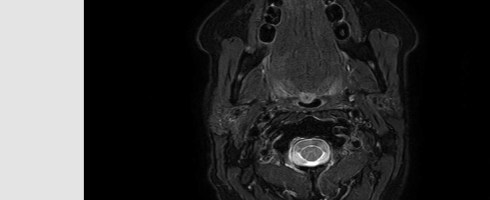

And this my friends, is my new left hip!

Incredible isn’t it?

This x-ray also shows a deterioration of the bone in my right hip, in line with the early stage Avascular Necrosis reported in the MRI a few weeks back.